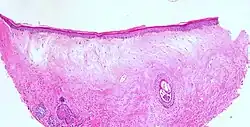

Typische histopathologische Merkmale des Lichen sclerosus sind eine Atrophie der Epidermis mit vakuolärer Degeneration der Keratinozyten (hornbildende Zellen der Epidermis) in der basalen Zellschicht und Sklerose der korrespondierenden Dermis. Der Sklerosezone grenzt zur Tiefe ein zumeist bandartig angeordnetes Entzündungsinfiltrat aus Lymphozyten an. Weitere mögliche Veränderungen sind eine unregelmäßige Akanthose (Verbreiterung des Stratum spinosum der Epidermis) und Hyperkeratose der Epidermis (hypertrophische Form), auf behaarter Haut mit Hyperkeratosen der Haarfollikel.[19]

In extragenitalen Läsionen fehlt häufig die Atrophie und das Entzündungsinfiltrat kann eosinophile Granulozyten enthalten. In der Dermis zeigen sich hier häufiger aufgeweitete kleine Blutgefäße.[20][21] Klinisch bullöse Läsionen gehen mit einem dermalen Ödem bis hin zur subepidermalen Blasenbildung einher.

Lichen sclerosus (atrophische Form) -